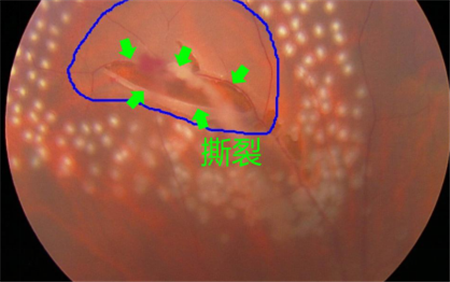

視網膜退化以及撕裂、后玻璃體脫落、葡萄膜炎、糖尿病或者黃斑變性引起的眼底出血等,可導致飛蚊癥產生,這種情況就屬于惡性飛蚊。雖然飛蚊本身并不會導致眼睛失明,但這些原發疾病若不及時治療,失明的風險卻是非常大的。

所以在出現飛蚊癥時,建議上醫院做個檢查,看看屬于哪一種飛蚊。尤其是突然出現大量飛蚊、閃光,并伴隨視力下降或者視野缺損的情況,更需要及時就醫。在上海眼科醫院排名治療惡性飛蚊需要結合患者的原發疾病進行治療,比如由視網膜裂孔導致的飛蚊癥,需要通過激光治療將裂孔封閉,從而避免視網膜進一步脫落。